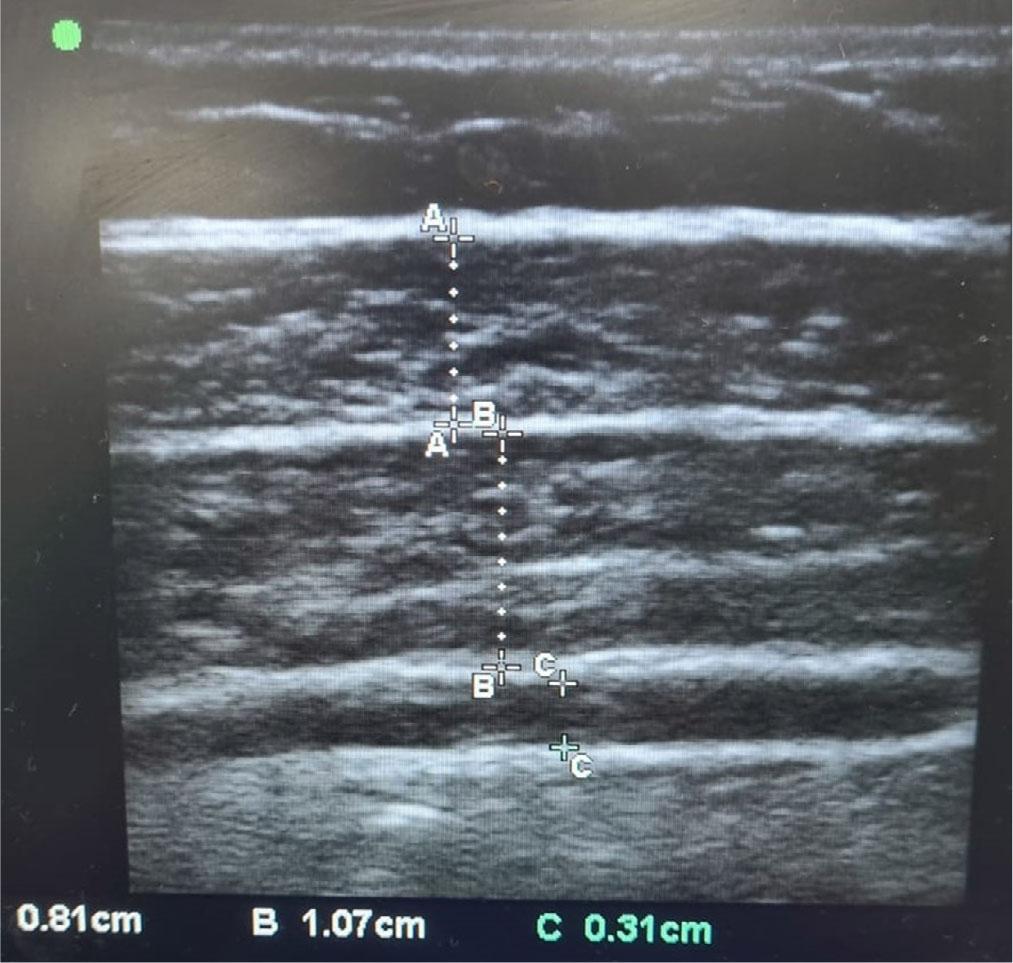

The thickness of the EO, IO, and TA muscles was measured using USG. After placing the patients in the supine position, a linear ultrasound probe, operating at 9–12 MHz, using B-mode imaging was placed perpendicular to the skin halfway between the iliac crest and the 12th rib along the anterior axillary line (Fig. 3). Muscle thickness was determined as the largest distance between the superficial and deep aponeuroses for each muscle. To ensure consistency and reduce observer bias, all measurements were performed by a single observer who was blinded to the patients’ CT findings and hand grip strength measurements.

Measurement of abdominal muscle thickness using ultrasonography (A – external oblique; B – internal oblique; C – transversus abdominis)